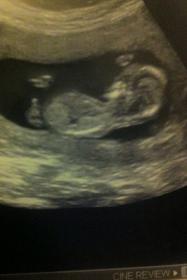

baby is 12 wks 4 days here. I would really like your opinion please!! I have already posted on another forum and would like to see if you lovely ladies think the same!

Attachment 1034Attachment 1035